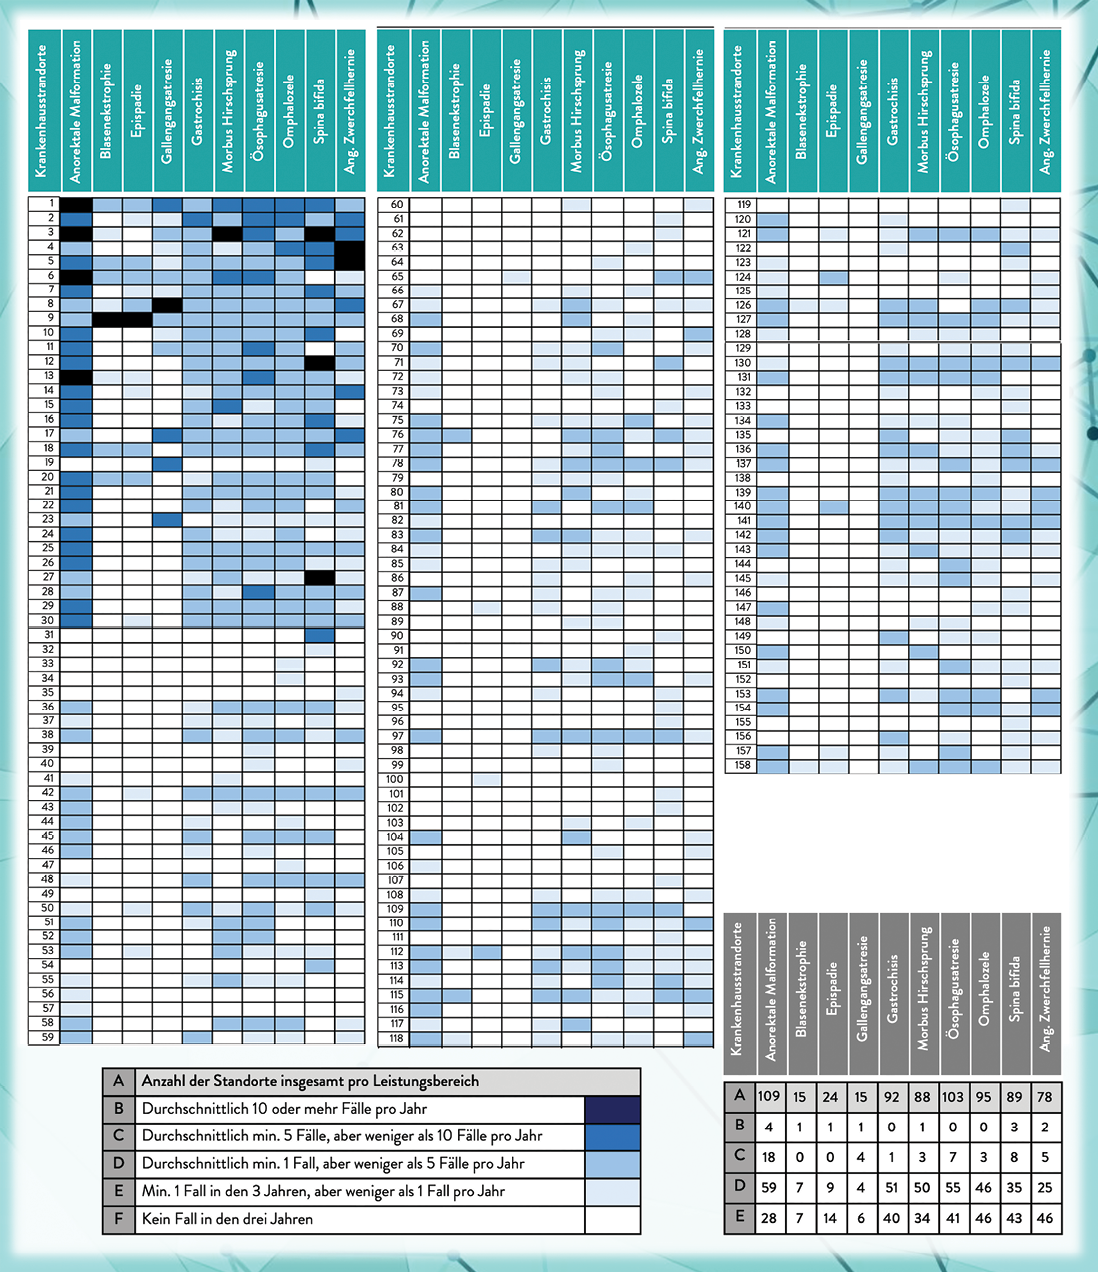

Krankenkassenabrechnungsdaten mit der Erfassung aller in Deutschland durchgeführten Korrekturoperationen zwischen 2020–2022 zeigen eine stark zersplitterte Versorgungslandschaft. Die in dem Zeitraum durchschnittlich durchgeführten 1.429 Korrekturoperationen verteilten sich auf 158 Krankenhausstandorte. Davon führten 127 (80 %) der Standorte bei keiner der komplexen Fehlbildungen mindestens fünf Korrekturoperationen pro Jahr durch. Von den verbleibenden 31 Kliniken führten 25 nur für ein oder zwei Fehlbildungen mindestens fünf Korrekturoperationen durch. Die Mindestzahl von zehn Korrekturoperationen pro Jahr erreichte bei Ösophagusatresie, Gastrochisis und Omphalozele bundesweit keine Klinik [9]. Mehr als die Hälfte der in dem Untersuchungszeitraum an der Korrekturoperation für Morbus Hirschsprung partizipierenden Standorte hatte nicht einmal einen Fall in jedem Jahr.

Abb. 2: Durchschnittliche jährliche Fallzahl pro Standort, ermittelt aus den Jahren 2020, 2021 und 2022 für die Korrekturoperationen von zehn verschiedenen komplexen Fehlbildungen.